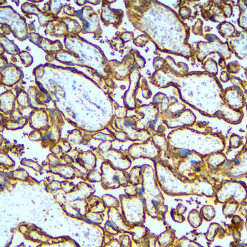

Since 1994, Diagnostic BioSystems Inc. has been committed to enhancing immunohistochemistry results by providing innovative anatomic pathology reagents and systems to improve the practice of pathology. Since our inception, our prime focus has been to provide high quality products and exceptional customer service and support. Read More >